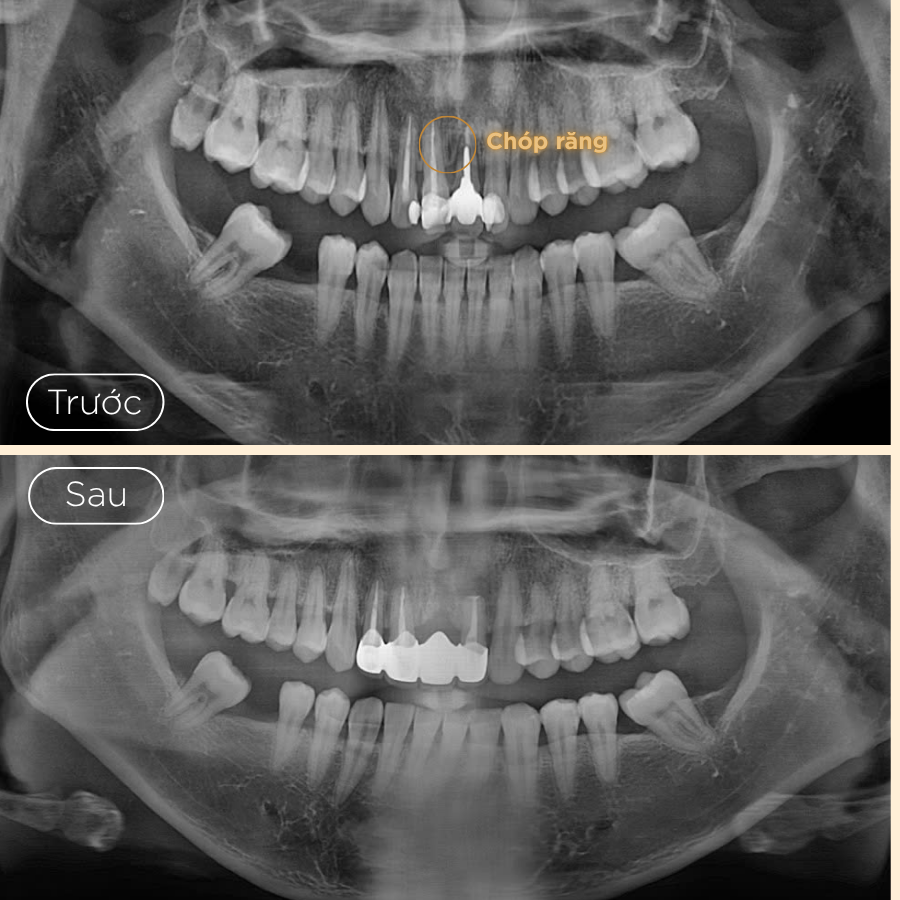

- 1. Khám và tư vấn: Bác sĩ sẽ thăm khám lâm sàng và chụp X-quang để xác định mức độ nhiễm trùng và vị trí chính xác của vùng viêm. Điều này giúp bác sĩ lên kế hoạch phẫu thuật một cách chi tiết và an toàn.

- 3. Gây tê, tiếp cận và cắt chóp chân răng: Trước khi bắt đầu quy trình, vùng cần điều trị sẽ được gây tê để đảm bảo bạn không cảm thấy đau hoặc khó chịu trong suốt quá trình điều trị. Bác sĩ sẽ tạo đường vào vị trí chóp răng bị nhiễm trùng, loại bỏ khoảng 2mm phần chóp răng, đồng thời làm sạch mô viêm xung quanh.

- 4. Trám ngược chóp răng và khâu đóng vết mổ: Sau khi vùng viêm đã được làm sạch, phần cuối của ống tủy sẽ được trám bít ngược lại bằng vật liệu chuyên dụng để ngăn chặn sự tái nhiễm trùng. Vết mổ sẽ được khâu đóng và lành lại trong vài tuần sau đó.